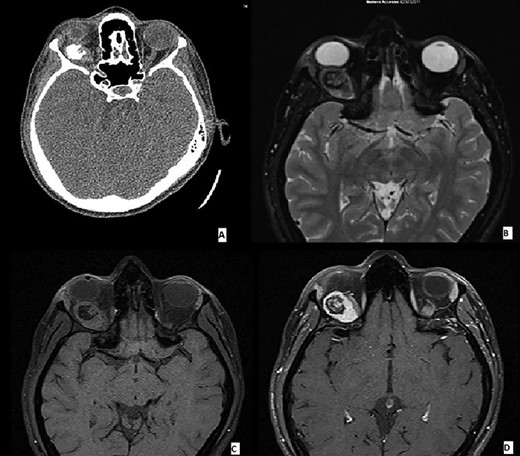

A 30-year-old Caucasian female without any past medical illness presented with an endorbital mass of the right eye, without proptosis. Physical examination revealed a decreased right visual acuity. No abnormality of the left eye was detected. Computed tomography (CT) and magnetic resonance imaging (MRI) scans revealed a well-defined right intrasonic mass, in the upper-external quadrant with optical nerve displacement without involvement of it. The endorbital mass was adherent to the superior rectus muscle with a cleavage plane. CT scans demonstrated an ovoidal soft tissue mass with central calcification. T1 and T2 weighted images showed an oval tumor with iso-hyperintense signal with a calcified central component. Enhanced T2 weighted images demonstrated an omogenous tumoral enhancement except for the central calcified part (Fig. 1). These findings have led to a radiological-suggested differential diagnosis between vascular malformation, cavernous hemangioma and solitary fibrous tumor.

(A–D) Imaging features of MCS: CT scans demonstrated an ovoidal soft tissue mass with central calcification (A), T2 (B) and T1 (C) weighted images showing an oval tumor with iso-hyperintense signal with a calcified central component. Enhanced T1 weighted image demonstrating an omogenous tumoral enhancement except for the central calcified part (D).